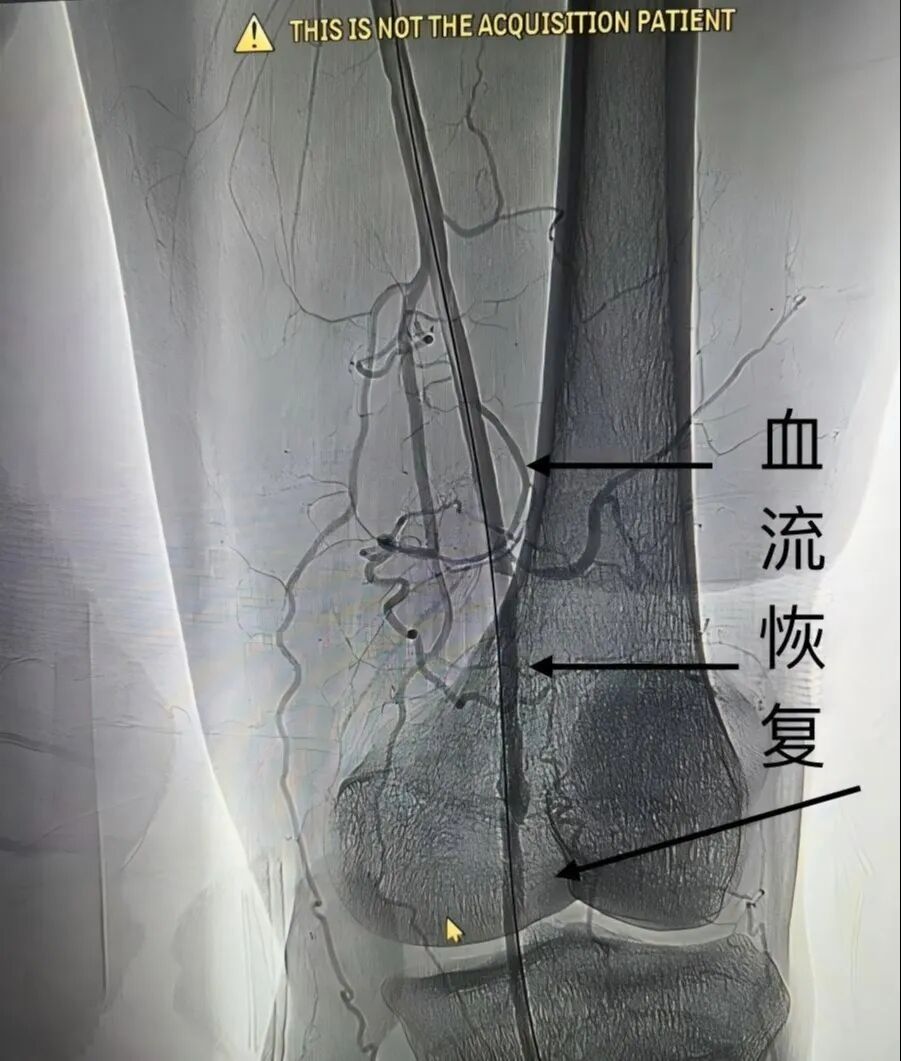

澧县中医医院介入科为该患者运用了目前领先的“下肢动脉斑块旋切术+药物涂层球囊扩张技术”,在精准清除斑块的同时,有效恢复血流,并避免了永久性支架的植入。

(▲术中)

(▲术后)